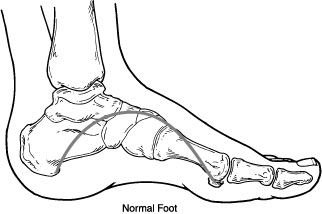

Charcot foot is a condition causing weakening of the bones in the foot that can occur in people who have significant nerve damage (neuropathy). The bones are weakened enough to fracture, and with continued walking the foot eventually changes shape. As the disorder progresses, the joints collapse and the foot takes on an abnormal shape, such as a rocker-bottom appearance.